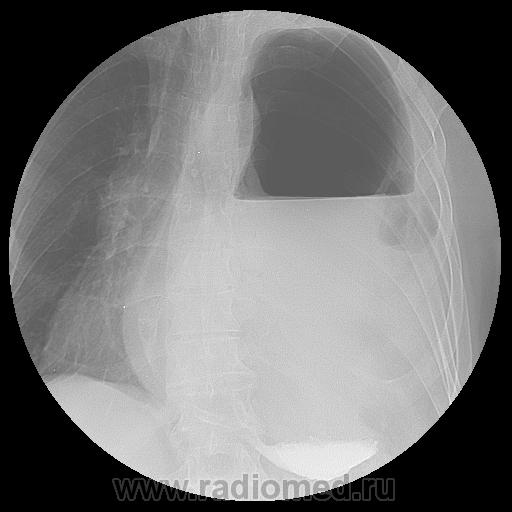

Извеняюсь с задержкой, проблема с интернетом, данный пациент поступал ещё пол года назад, с предворительным диагнозом: Диафрагмальная грыжа слева? Тотальный гидропневмоторакс слева? Мы просто дали ему рентген-контрастное под контролем скопии.

А вот R-контроль после операции: